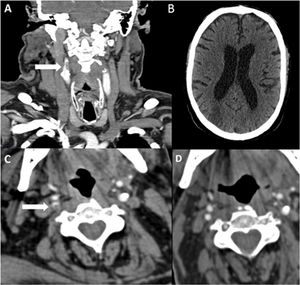

Paciente 13. A) Angio-TC axial, trombosis endoluminal sobre placa de ateroma en el arco aórtico ascendente. B) Reconstrucción coronal angio-TC. C) Radiografía de tórax, infiltrado bilateral difuso en lóbulos pulmonares inferiores y atelectasias laminares en el lóbulo inferior. D) Reconstrucción sagital de angio-TC de la trombosis endoluminal sobre placa de ateroma en el arco aórtico.